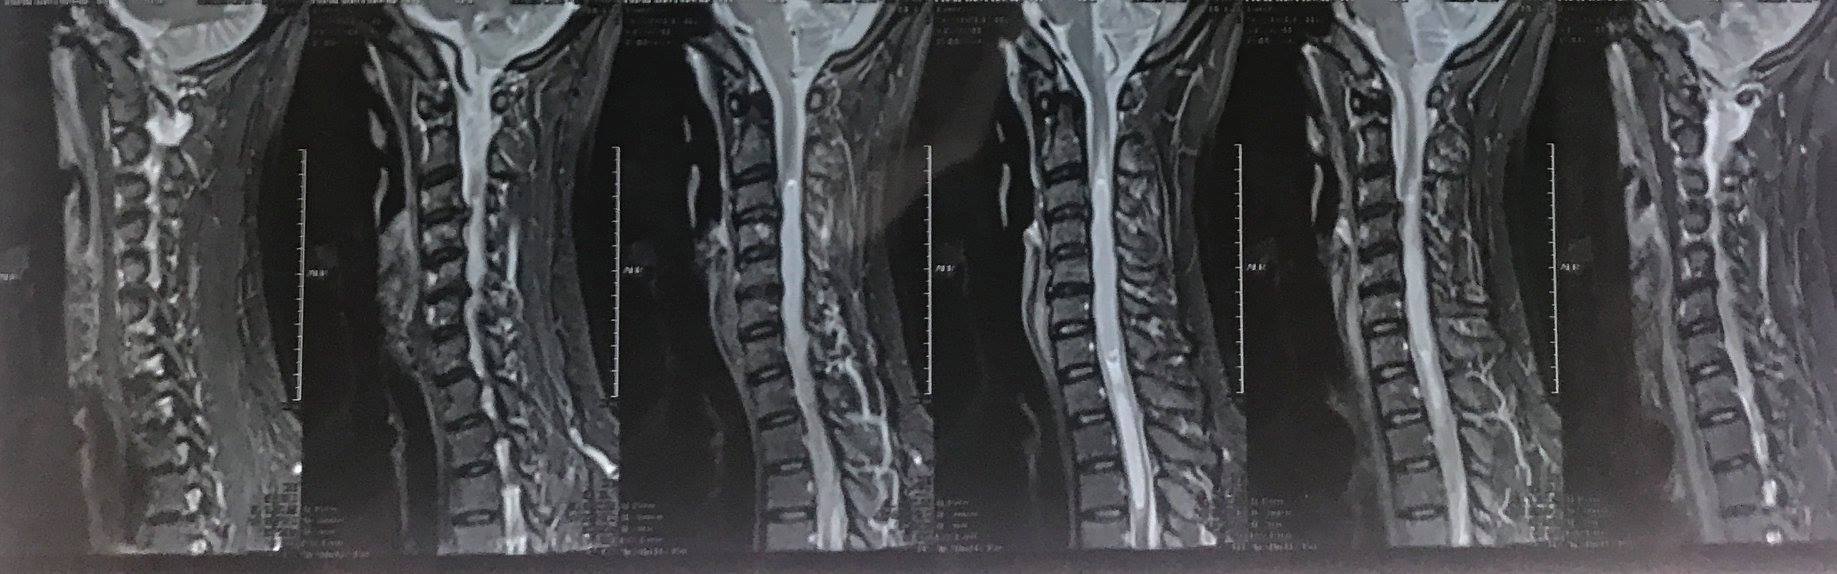

Bệnh nhân nữ 44 tuổi với biểu hiện tê bì dị cảm và yếu tứ chi trên 1 năm và đã đi nhiều nơi khám và điều trị với chẩn đoán: viêm tủy cắt ngang nhưng thực tế, bệnh nhân bị u tế bào màng lót ống nội tủy.

Bệnh nhân đến khám khi đã giảm cảm giác và yếu tứ chi, đi lại khó khăn: khối u lớn, kéo dài, trong tủy... Đây là một nỗi khiếp đảm cho các phẫu thuật viên.

Bệnh nhân này có khối u kéo dài từ C3 đến D3 là 8 đốt sống. Khối u bao gồm cả u đặc và nang. Trước đây, việc mở tủy rất khó khăn vì có thể gây liệt tứ chi do tổn thương tủy. Ngày nay, với kính vi phẫu phóng đại hàng chục lần và hệ thống cảnh báo thần kinh trong mổ mà có thể mở tủy lấy u được. Nhưng nếu không mổ, bệnh nhân sẽ bị liệt tứ chi và rối loạn hô hấp.